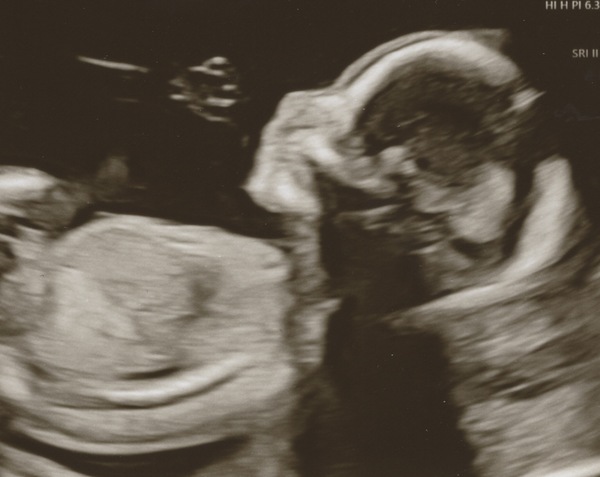

Beautiful scan @PurplePansy05 - a wiggly baby is a good baby!

My scan this morning was so wonderful. I was very weepy the whole time, I loved seeing all the anatomy up close. Everything looked good and the baby was beautiful. I also had to get up and take a walk, and have a sugary treat for the sonographer to get a good view of the spine, but the baby cooperated and we got it all checked out!